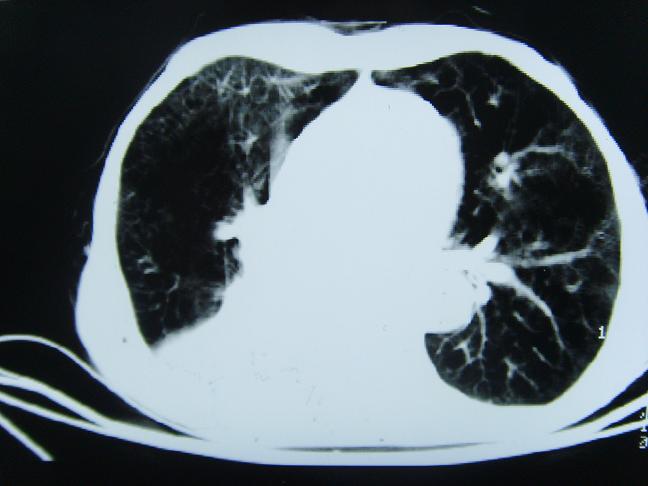

考虑  右肺新生物伴右下肺阻塞性肺炎,肺不张.右侧胸腔积液

考虑:右侧中心型肺癌伴下肺肺不张。

1)右肺中央型肺癌伴右肺下叶肺不张。2)慢性支气管炎,肺气肿。3)右侧胸腔积液。

1)右肺中央型肺癌伴右肺下叶肺不张。2)慢性支气管炎,肺气肿。3)右侧胸腔积液

右肺中央型肺癌伴右肺下叶肺不张。慢支肺气肿。右侧胸腔积液。